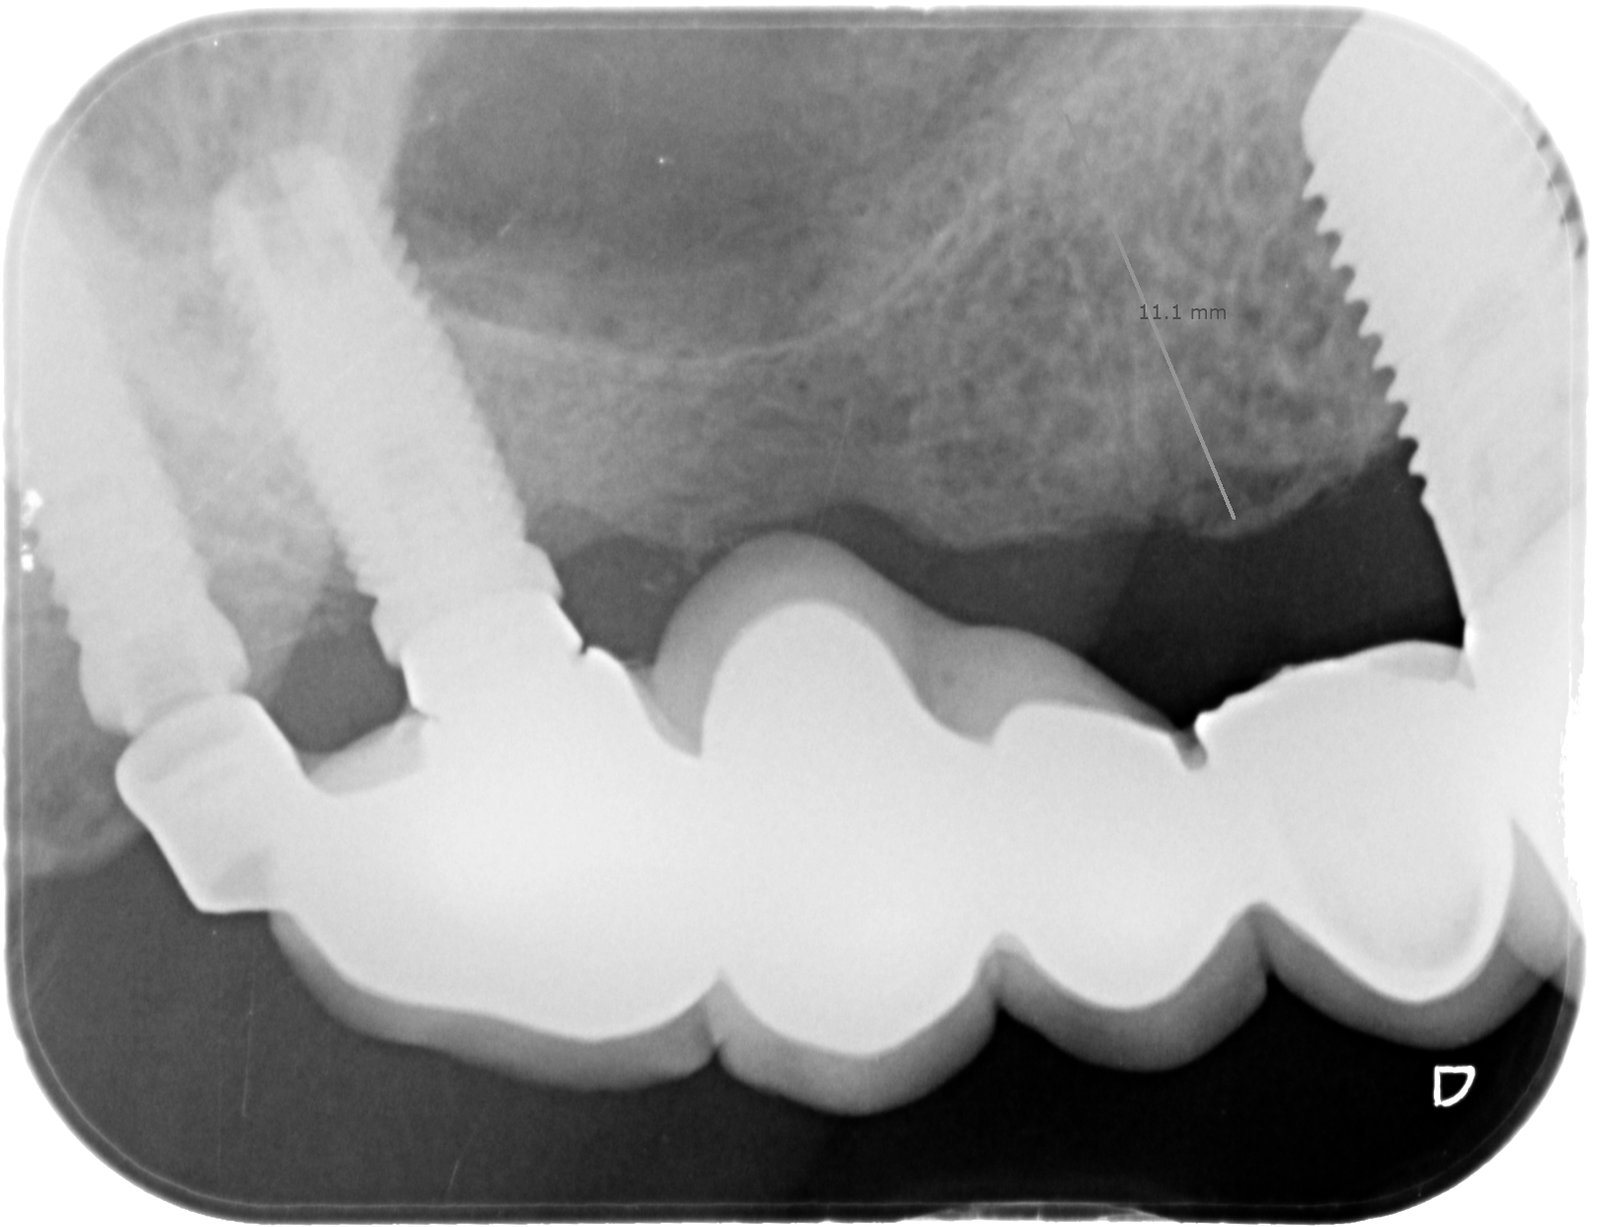

Al paciente se le ha colocado un implante en 13 y se va a rehabilitar con ese implante que tiene en "16". El ultimo implante tiene un tornillo fracturado y [...]